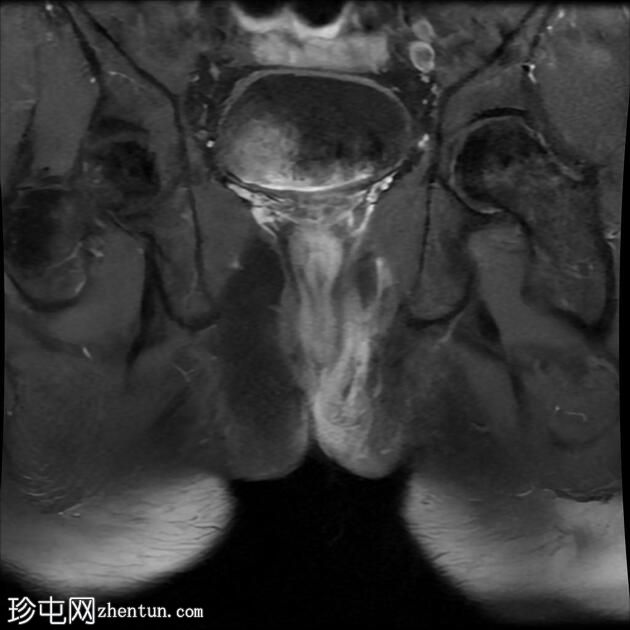

MRI

轴向位T2

脂肪饱和度

冠状位T1

一条68毫米厚的强化通道始于左侧肛周区域,向上穿过肛门内外括约肌,在2点钟方向开口于肛管。

无脓肿形成。

MRI成像特征与所述左侧经括约肌肛周瘘相符。